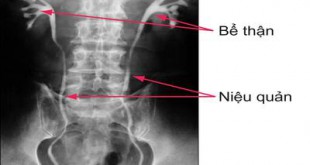

Các cấu trúc trên không được thấy rõ trên hình ảnh X quang thông thường. Tuy nhiên, chúng sẽ được thấy rõ hơn khi chụp X quang hệ tiết niệu bằng cách tiêm thuốc cản quang vào cơ thể. Trong phương pháp này, thuốc cản quang sau khi được tiêm vào tĩnh mạch sẽ đi đến thận, được lọc và thải ra ngoài qua nước tiểu. Thuốc cản quang không cho tia X đi qua và do đó cấu trúc của thận, niệu quản và bàng quang sẽ xuất hiện rõ ràng với màu trắng trên phim X quang (xem hình). Những hình ảnh X quang chụp vùng bụng và chậu sau khi tiêm thuốc cản quang gọi là hình ảnh X quang hệ tiết niệu bằng đường tĩnh mạch (IVU).